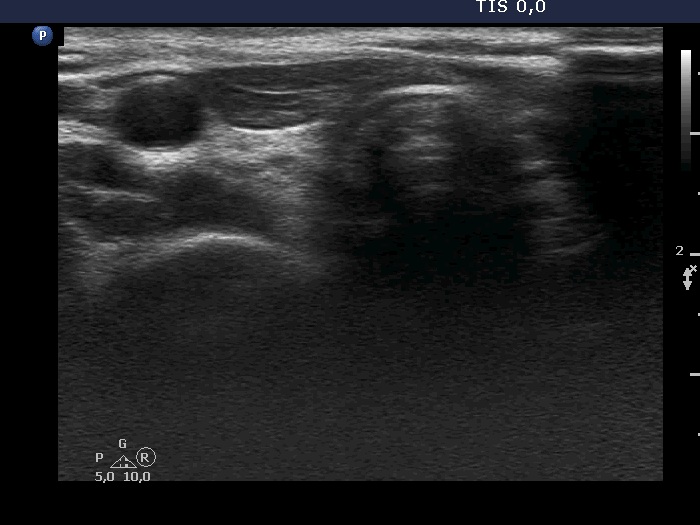

Ultrasound. Connective tissue replaced the thyroid parenchyma in both thyroid beds. There was a hypoechoic mass in the lower part of the right thyroid bed dorsal to the carotid artery. The lesion was a mixed, dominantly solid nodule and had microcalcifications.